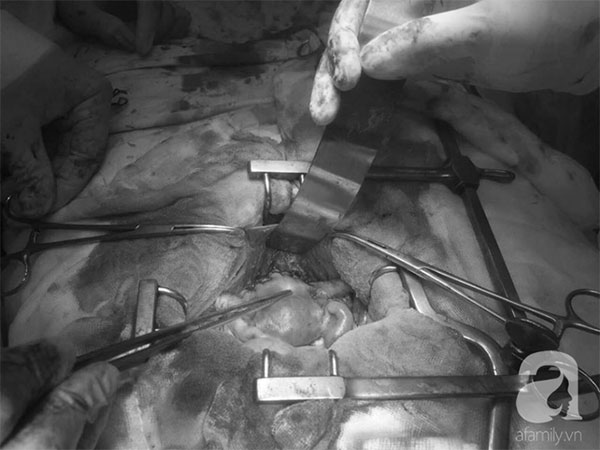

Ngày 13/12, các bác sĩ đã tiến hành phẫu thuật cắt bỏ tử cung, các phần phụ và nạo hạch. Sau mổ, sức khỏe bệnh nhân ổn định. Hiện chị N. đang chờ kết quả sinh thiết khối u để xác định chính xác kế hoạch điều trị tiếp theo.

Sau 4 giờ căng thẳng, kíp mổ đã lấy toàn bộ khối bướu nặng chèn ép xương cùng cụt đến 4kg. Trong quá trình phẫu thuật, nhiều lần mạch và huyết áp bệnh nhân không đo được, mất gần 3 lít máu.

Ca mổ kết thúc, toàn bộ kíp mổ đổ quỵ, phòng mổ như một bãi chiến trường thực sự với hàng trăm miếng gạc to nhỏ và nhiều vật dụng được mang ra dùng.